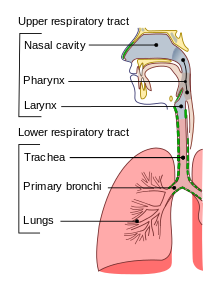

בדומה לנגיפי קורונה אחרים התוקפים את האדם, נגיף זה מסוגל לגרום לזיהומים של דרכי הנשימה העליונות והתחתונות. התסמינים יכולים להיות קלים (שפעת פשוטה) אך גם חמורים (דלקת ריאות), הן באנשים בריאים כמו גם באלה עם מערכת חיסון פגועה. ההעברה וההדבקה של SARA CoV-2, נעשית בעיקר על ידי טיפות הנפלטות במהלך נשיפת אוויר. במהלך השלבים המוקדמים של COVID-19, התסמינים יכולים להיות לא ספציפיים, ולדמות לזיהומים אחרים של מערכת הנשימה, דוגמת שפעת. אם תוצאת איתור פתוגנים אחרים של מערכת הנשימה מתקבלת שלילית, יש צורך לבחינה ספציפית של הדבקה ב-SARS CoV-2. נגיף זה יימצא בריכוזים הגבוהים ביותר באזור הלוע העליון (nasopharynx) שהוא חלקו של הלוע הממוקם מעל ומאחורי החך הרך, במהלך 3–5 ימים ראשונים של מחלה תסמינית, וככול שהמחלה מתקדמת הנגיף מתמעט בדרכי הנשימה העליונות, בה בשעה שדגימות מדרכי הנשימה התחתונות, כגון ליחה, חומר הננשף מצינור הנשימה (tracheal aspirate), נוזל ברונכו-אלבאולרי) תהיינה מקור סביר יותר לזיהוי SARS CoV-2.